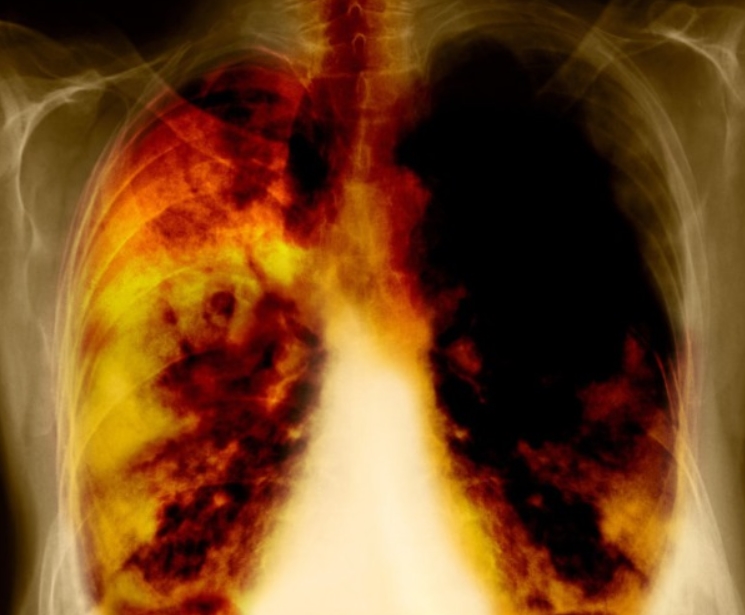

흉부CT는 말 그대로 가슴 속을 정밀하게 들여다보는 검사입니다. 예전에는 엑스레이로도 충분하다고 생각했지만, 지금은 보이지 않는 작은 변화들이 병을 가르는 시대가 되었죠. 실제로 제 지인은 계속 기침이 나서 감기인 줄 알았는데, 병원에서 흉부CT를 찍어보니 기관지염과 초기 폐렴이 동시에 진행 중이었습니다. 엑스레이로는 전혀 보이지 않던 부분이었어요.

이 검사는 X선을 여러 각도에서 투사해 가슴 속을 단면으로 나누고, 컴퓨터가 이를 조합해 입체적으로 보여줍니다. 흉부ct로 볼수있는 질환 폐, 기관지, 심장, 혈관, 흉막, 림프절, 늑골까지 모두 관찰할 수 있어요. 몸을 절개하지 않고 내부를 볼 수 있으니 환자에게 부담이 적습니다. 조영제(혈관이나 염증 부위를 선명하게 보여주는 약물)를 사용하는 경우에는 정맥으로 주입하기도 하지만, 대부분은 통증이 거의 없습니다.

엑스레이는 가볍고 빠른 검사예요. 병원에서 기침이나 흉통이 있으면 가장 먼저 찍는 사진이죠. 하지만 엑스레이는 가슴 속 장기를 한 번에 찍기 때문에, 여러 구조가 겹쳐 보입니다. 그만큼 정확한 구분이 어렵고, 미세한 결절이나 염증은 지나치기 쉽습니다.

흉부CT는 이야기가 달라요. 얇게 자른 단면을 수백 장 촬영하기 때문에, 작은 병변도 놓치지 않습니다. 마치 산 전체를 한 장의 사진으로 보는 엑스레이와 달리, CT는 나무 한 그루 한 그루를 자세히 보는 느낌이에요. 예전에 병원에서 일했던 친구 말로는, 엑스레이에 아무 이상이 없던 환자가 CT에서 폐암 초기 진단을 받은 경우도 많았다고 합니다. 그만큼 CT는 정밀한 탐색 도구입니다.

흉부ct로 볼수있는 질환 폐질환뿐 아니라 심장과 혈관, 흉막, 림프절, 뼈 구조까지 한 번에 보여줍니다. 폐렴, 결핵, 폐기종, 기관지확장증, 간질성 폐질환 같은 호흡기 질환은 기본이고, 폐에 생긴 작은 결절이나 혹도 세밀하게 확인할 수 있습니다. 폐암이나 전이암처럼 초기에 증상이 거의 없는 병은 CT로 발견되는 경우가 많아요.

흉부CT는 병이 있는지 없는지를 넘어서, 병의 진행 정도와 주변 장기 침범 여부까지 보여줍니다. 예를 들어 폐암의 경우, 5mm 미만의 아주 작은 결절까지 찾아내고, 종양이 혈관이나 기관지에 닿았는지도 확인합니다. 초기에 잡아내면 완치율이 크게 높아지죠.

또한 폐렴이 감염인지, 결핵성인지, 종양에 의한 것인지도 구분할 수 있습니다. 엑스레이에서는 그냥 ‘흐린 그림자’로만 보이던 것도, CT에서는 염증의 경계와 내부 구조까지 뚜렷하게 드러납니다.